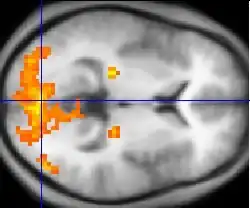

Neuroimagem

A ressonância magnética é a ferramenta investigativa de escolha para cânceres neurológicos, pois tem melhor resolução do que a TC e oferece uma melhor visualização da fossa posterior. O contraste fornecido entre matéria cinza e branca torna a ressonância magnética melhor opção para muitas condições do sistema nervoso central, incluindo doenças desmielinizantes, demência, doença cerebrovascular, doenças infecciosas e epilepsia.[30] Uma vez que muitas imagens são retiradas em milisegundos, mostra como o cérebro responde a diferentes estímulos, permitindo que os pesquisadores estudem as anormalidades cerebrais funcionais e estruturais em distúrbios psicológicos.[31] A RM também é utilizada na cirurgia estereotáxica guiada por MRI e radiocirurgia para o tratamento de tumores intracranianos, malformações arteriovenosas e outras condições tratáveis cirurgicamente usando um dispositivo conhecido como N-localizer.[32][33][34][35][36][37][38][39][40][41][42][43][44][45]